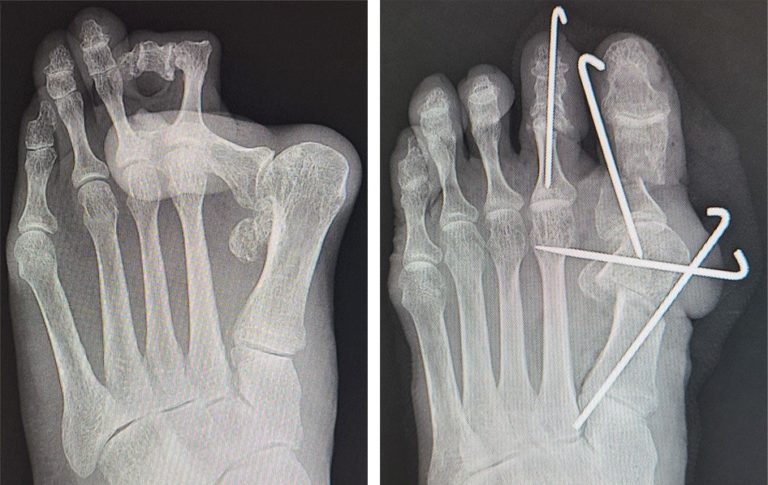

- 骨切り術:外科医は骨に小さな切り込みを入れ、ピン、ネジ、またはプレートを挿入して骨と関節の位置を再調整します。

- 関節形成術:この手術では、外科医は足の指の関節の拡大した部分を切除して、骨の間のスペースを増やします。また、インプラントを埋入することもあります。

- 関節固定術:外科医は関節の患部を除去し、ネジ、ピン、またはプレートを使用して骨が治癒するまで所定の位置に保持します。医師は、重度の関節炎や重度の外反母趾を患っている人にこの種の手術を勧めることがよくあります。